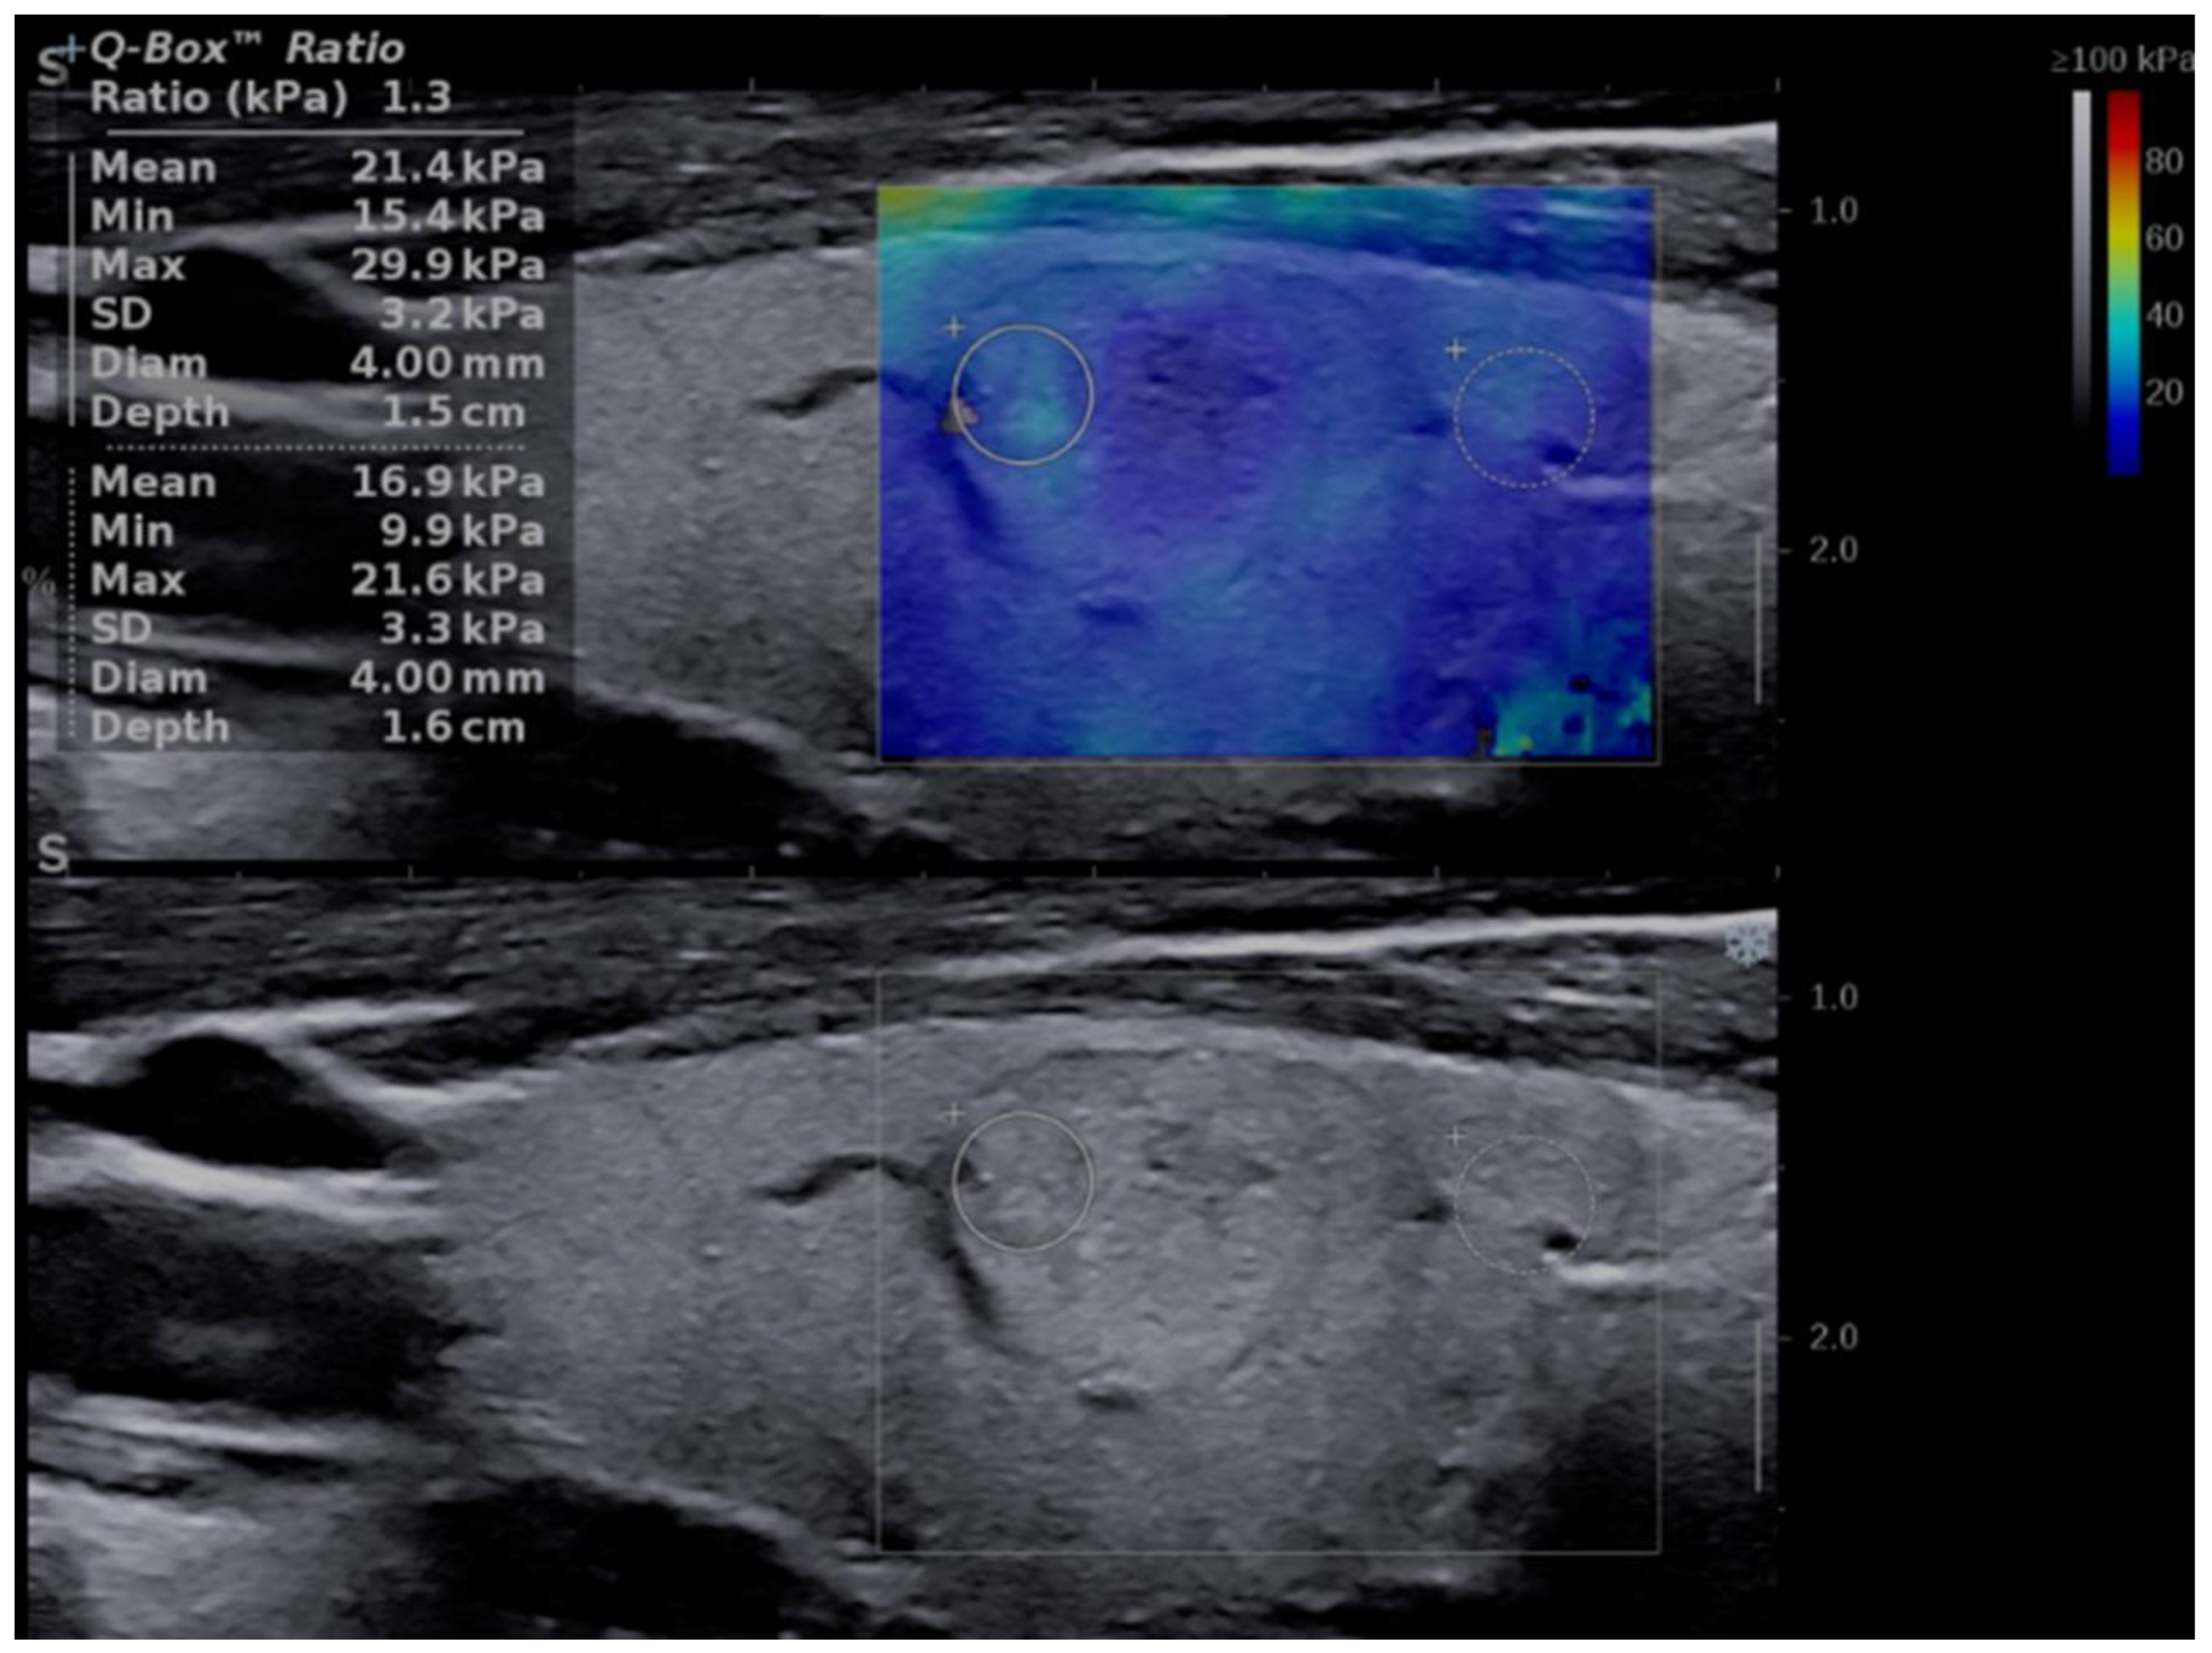

An upgrade of the risk category was made in eight cases with increased stiffness, defined as values of Mean EI > 30.5 kPa. Six cases were upgraded from low to intermediate risk and ten cases from intermediate to high risk (see Figure 4).

Figure 4.

Risk upgrade from intermediate risk in B-mode to high risk in B-mode + SWE due to increased stiffness (Mean EI = 68.2 kPa). Pathology report confirmed PTC.